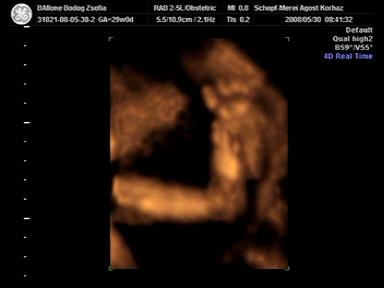

Reggel 8-ra mentünk az uh-ra, nagyon rendben volt minden, a szonográfus hölgy mindent teljes alapossággal megnéz, vesék, szívkamrák, hasfal, hólyag, gyomor, stb. stb., szóval tényleg profi! Kb. 17 percesre sikerült a DVD, amiből készítettem pár képet, amit majd megosztok veletek!

Benedek már 1436g (+/- 10%), így gondolom azért a 3 kilót elérjük szülésnél, bár, ha apából indulunk ki, akkor lesz az 4 kg is!

Hát kb. ezek vannak, és akkor most jöjjenek a képek a mi kis szemünk fényéről!